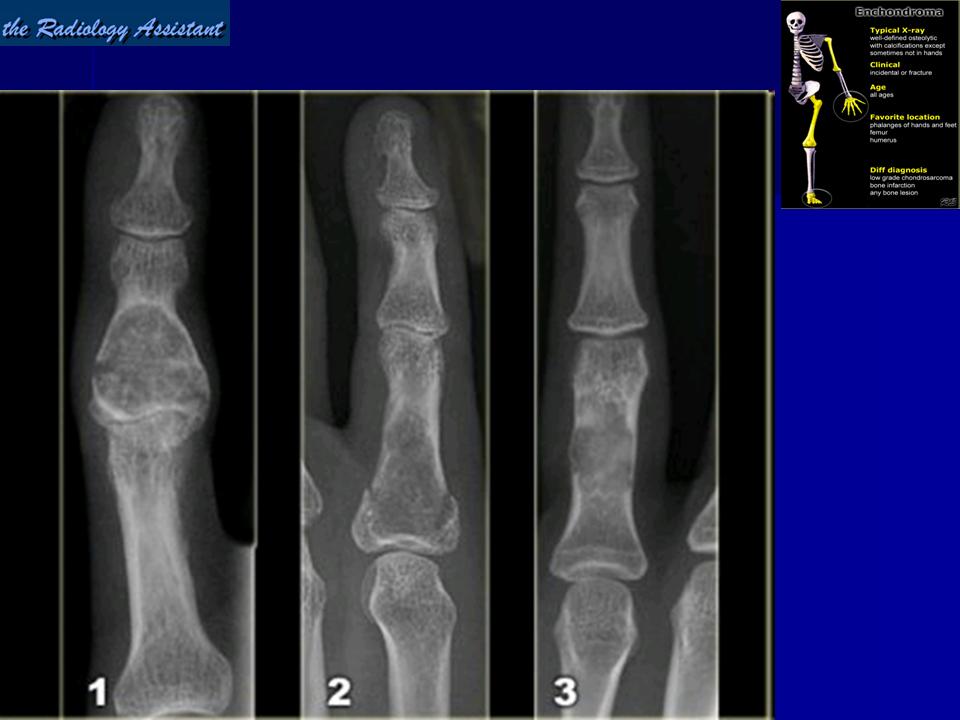

Энхондрома (син.: хондрома, центральная хондрома) — доброкачественная хрящевая опухоль, расположенная в костномозговом канале (интрамедуллярно). Встречается в 10 % случаев от общего числа доброкачественных опухолей костей. Считается, что она возникает из эктопически расположенных островков хряща, отщепившегося от пластинки роста на ранних этапах онтогенеза. В ряде случаев опухоль остается бессимптомной и обнаруживается случайно при рентгенологическом исследовании. В других случаях возникают боль и припухлость. Обычно болезненными становятся все энхондромы фаланг. Наиболее частая локализация: фаланги, главным образом, пальцев кистей, проксимальный конец плечевой кости, проксимальный или дистальный концы бедренной кости. При рентгенологическом исследовании в энхондроме определяются просветления с участками минерализации. Тень кости становится более широкой, кортикальный слой сохраняет целостность, но истончается. В редких случаях энхондрома имеет вид эксцентрически растущего экзофитного новообразования. Макроскопически опухоль представляет собой голубовато-белую полупрозрачную хрящевую ткань, в которую вкраплены желтоватые участки обызвествления. Опухоль состоит из отдельных хрящевых узелков, диаметр которых варьирует в пределах 1 см.

Рентгенологическая картина хондромы представляет четко очерченный опухолевый узел. Очаги минерализации в хондромах выглядят достаточно характерно и представлены очаговыми, глыбчатыми или кольцевидными , арочными отложениями извести. Полного разрушения кортикального слоя трубчатой кости с выходом опухолевых масс в мягкие ткани не наблюдается.

Энхондрома

Энхондрома.